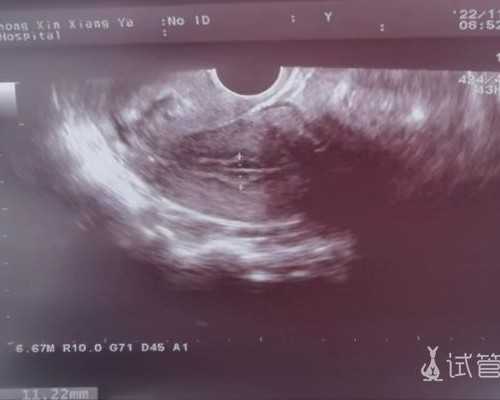

1、受测者胎龄满7周以上并提交当地医生开具注明胎龄7周以上的B超单;

4、专业医务人员采集受测者12MM血样(每管6MM),并放入香港化验所专属提供的K3血管

2、确认宝宝满7周,胚芽长度达10mm或以上。